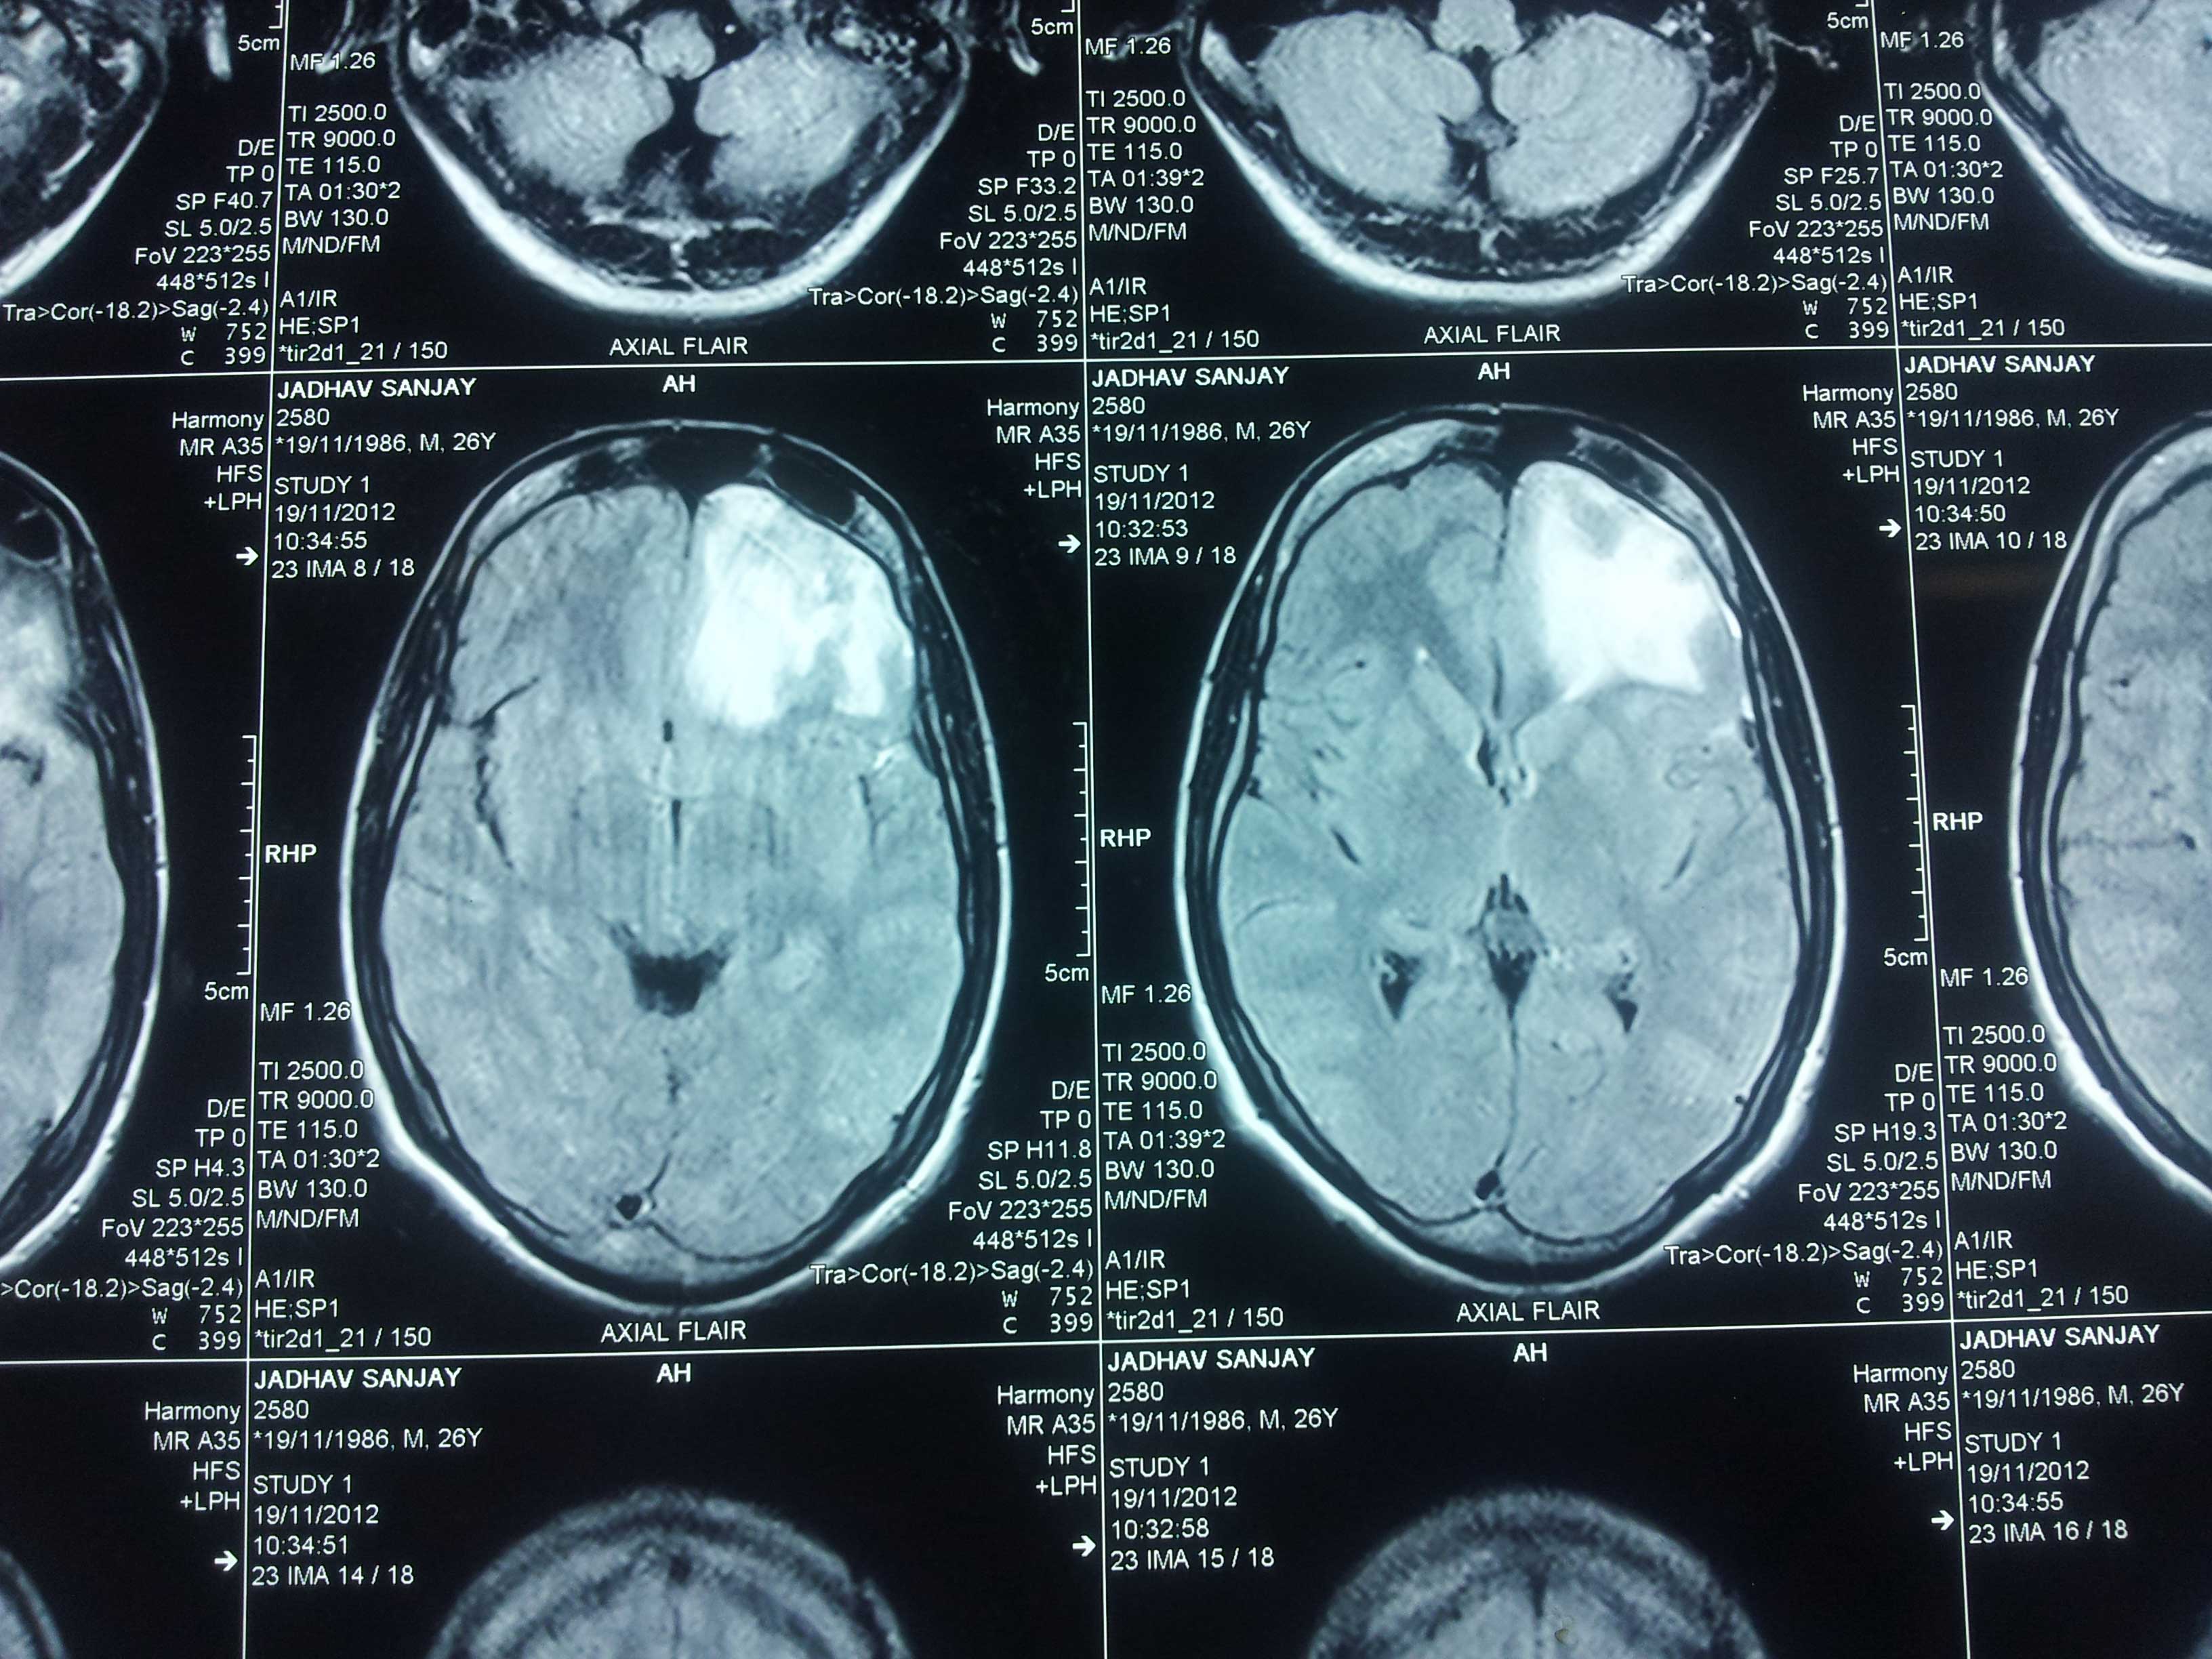

Brain Contusion Post OP CT of Bifrontal Contusion Brain X-Ray Bifrontal Contusion Pre OP intra op photo of contusion Brain Abscess Post OP 2 Clinical Brain Abscess Post OP 2 Clinical Brain Abscess Post OP 2 Clinical Brain Abscess Post OP 2 Clinical Brain Abscess Post OP 2 Clinical Brain Abscess Post OP 2 Clinical